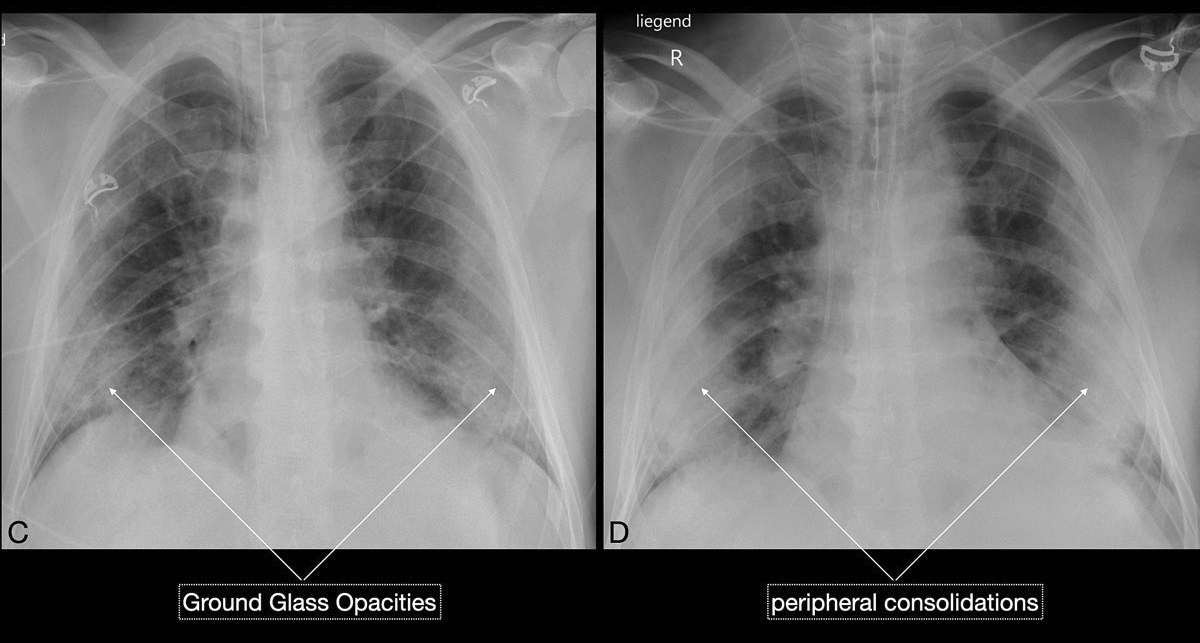

Figure 3 CD Chest x-ray (C) revealed extensive peripheral ground glass opacities, which became more consolidated (D) over the next 5 days.

Figure 3 EF Over time the clinical condition worsened, chest x-ray (E) demonstrated persisting, but mildly improving peripheral consolidations, and chest CT (F) demonstrated features of reparative organising pneumonia. The patient’s condition deteriorated and he died from septic and cardiogenic shock 12 days after intubation.